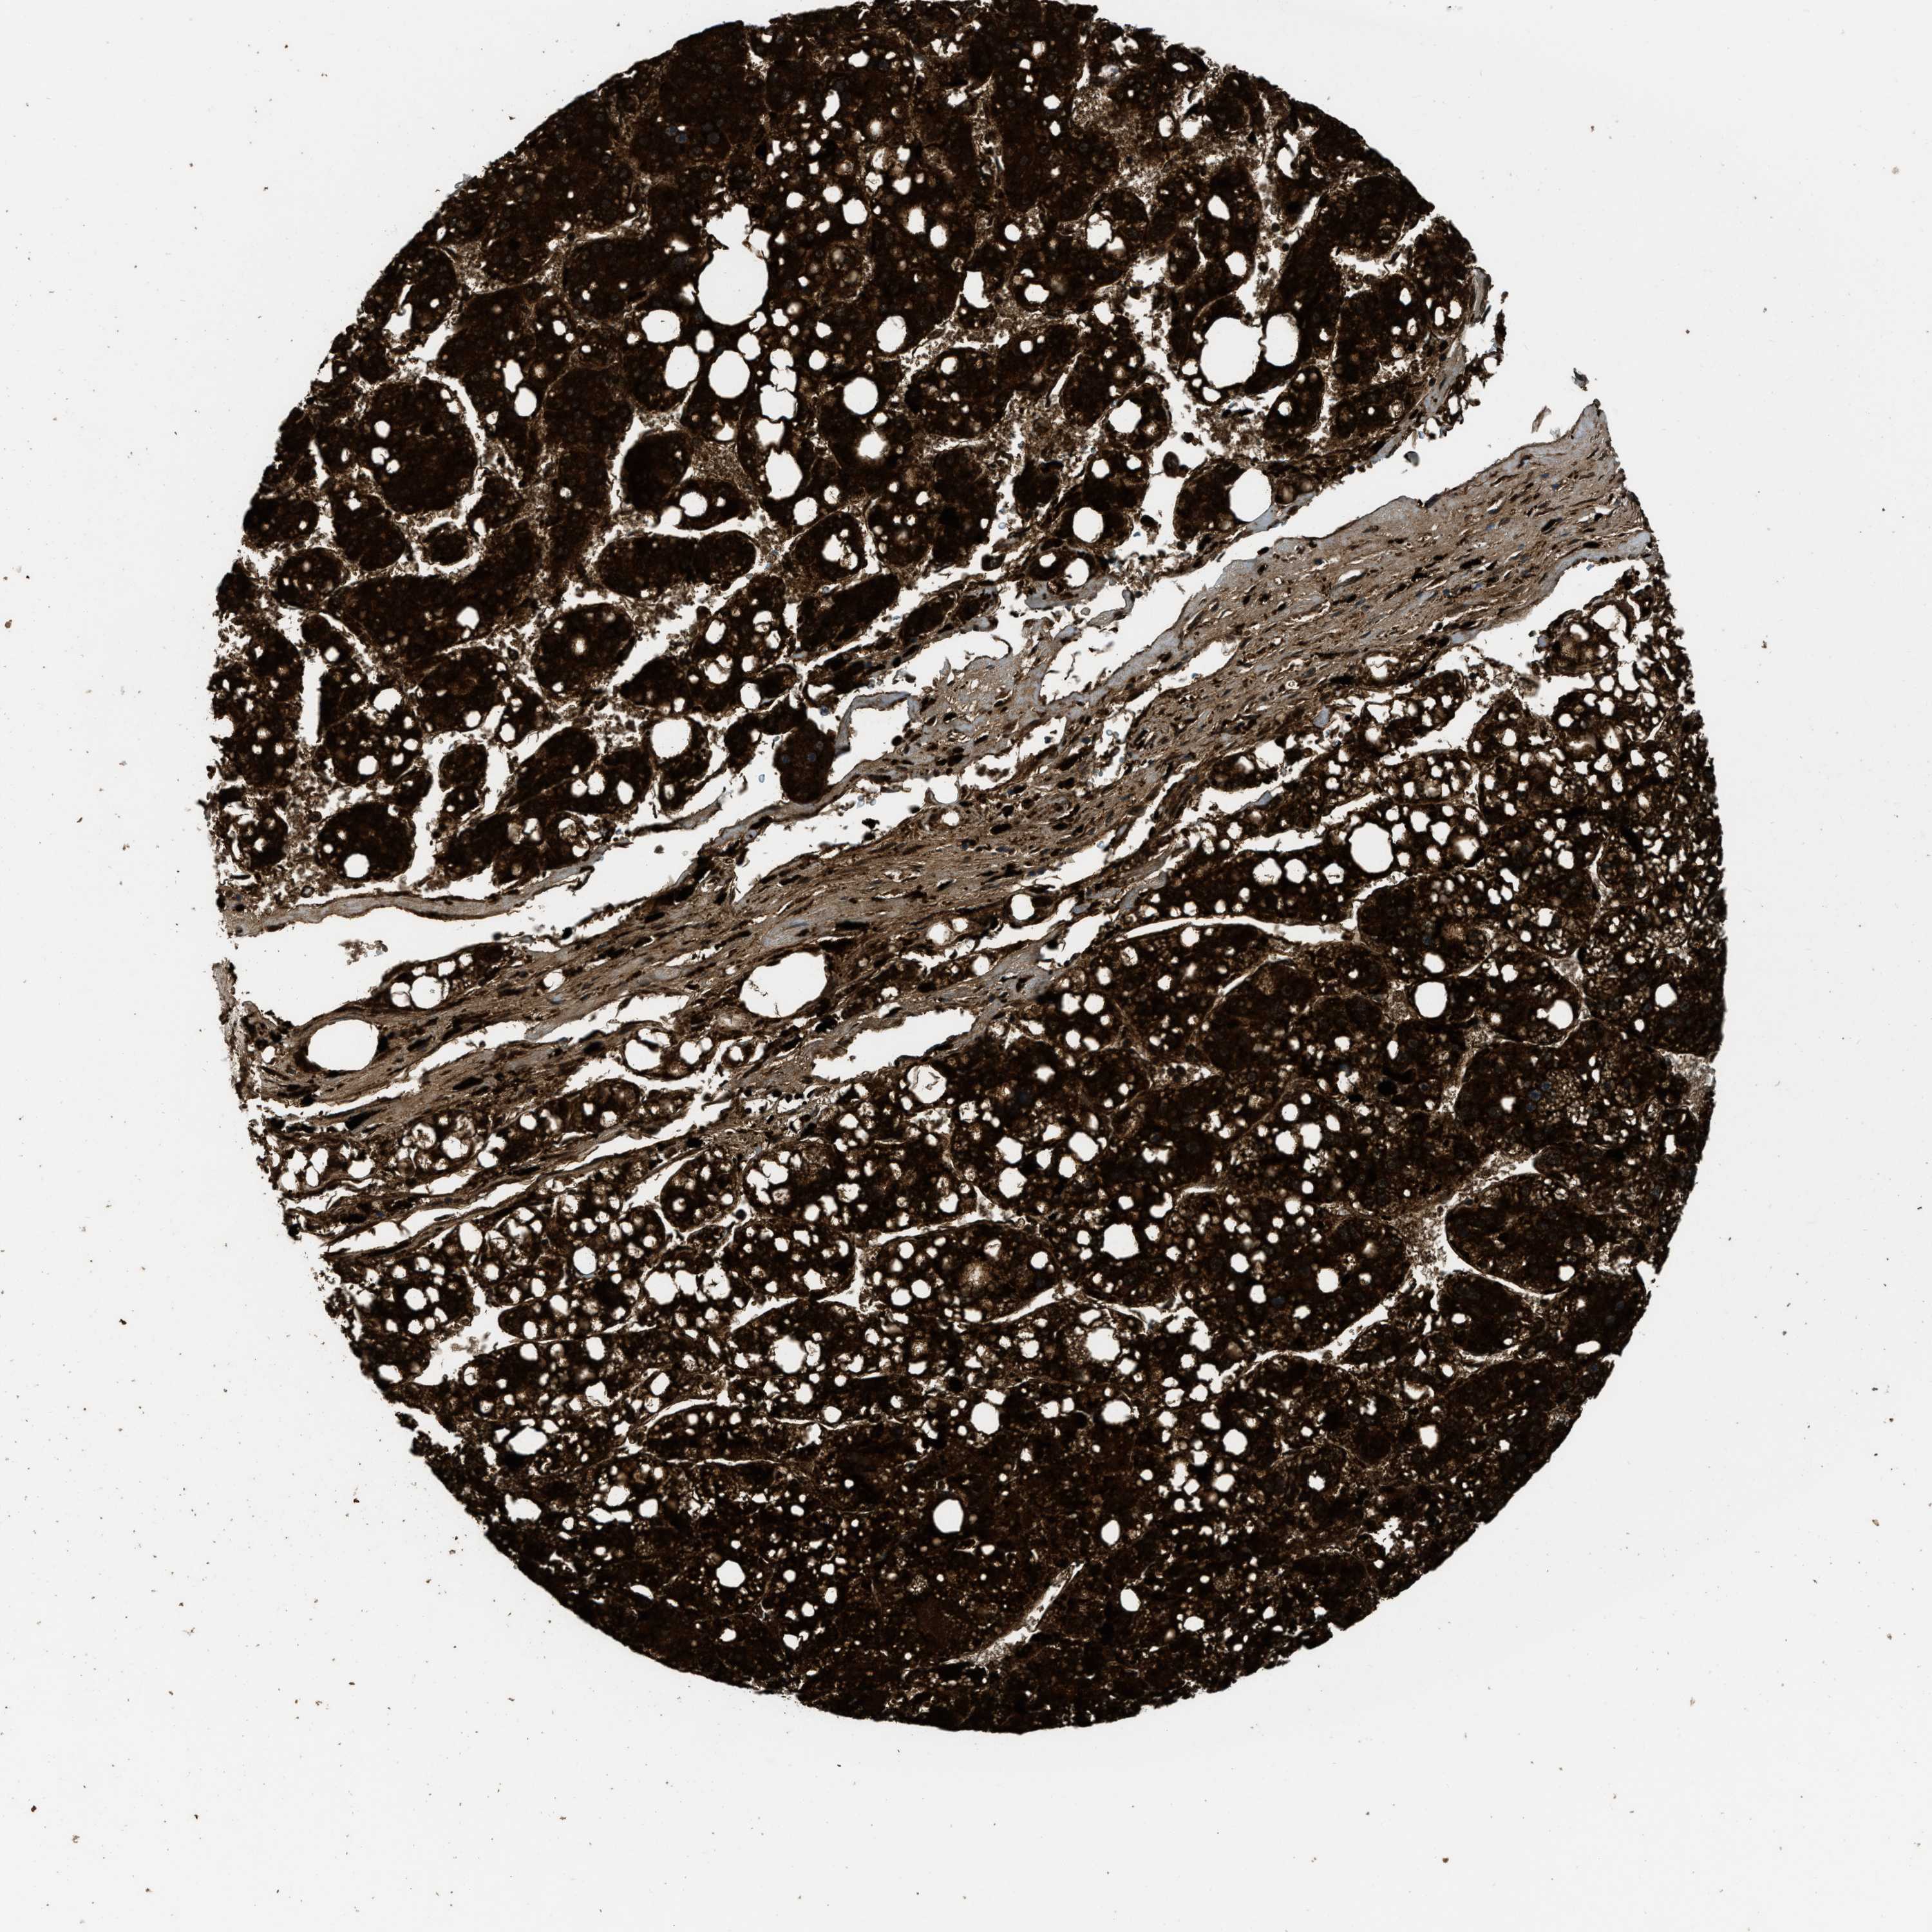

LIVER CANCER - Protein expressioni

A mouse-over function shows sample information and annotation data. Click on an image to view it in a full screen mode. Samples can be filtered based on level of antibody staining by selecting one or several of the following categories: high, medium, low and not detected. The assay and annotation is described here.

Antibody stainingi

Antibody staining in the annotated cell types in the current human tissue is reported as not detected, low, medium, or high, based on conventional immunohistochemistry profiling in selected tissues. This score is based on the combination of the staining intensity and fraction of stained cells.

Each image is clickable and will lead to virtual microscopy that enables deeper exploration of all samples and also displays staining intensity scores, fraction scores and subcellular localization as well as patient and tissue information for each sample.

Antibody HPA025226

Antibody CAB019296

Cholangiocarcinoma

Carcinoma, Hepatocellular, NOS